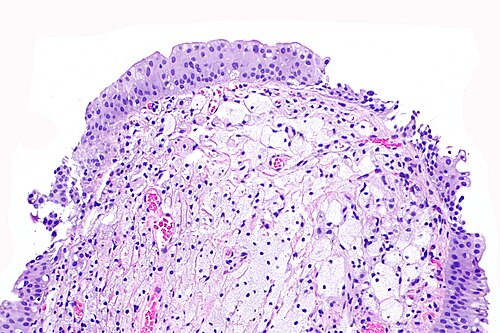

Primary image

Low magnification. H&E stain.